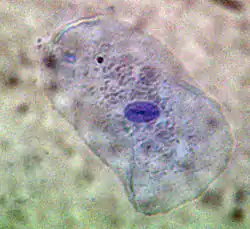

Mastzellen in der Zellkultur

Zu den herausragenden Ergebnissen dieser Doktorarbeit zählte die Entdeckung einer neuen Zellart. Ehrlich entdeckte im Protoplasma von vermeintlichen Plasmazellen eine Körnung, die sich mit Hilfe basischer Farbstoffe darstellen ließ. Er dachte, dass es sich um einen Zustand guter Ernährung handeln müsse, und nannte die Zellen „Mastzellen“. Ungewöhnlich für eine medizinische Doktorarbeit war der chemische Schwerpunkt: Ehrlich stellte in ihr das gesamte Spektrum der damaligen Färbetechniken und die Chemie der verwendeten Farbstoffe dar.

Vitalfärbung mit Methylenblau: Zelle der menschlichen Mundschleimhaut